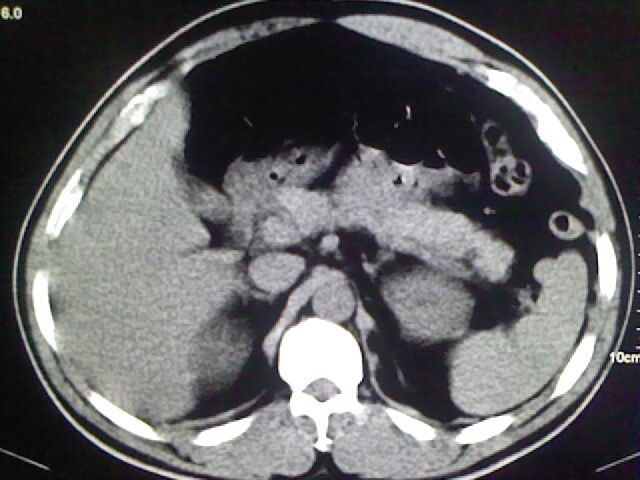

以下是引用zsl6918在2009-2-7 7:29:00的发言:[br]请提供介入的方式方法,肾及输尿管改变考虑与介入损伤有关,漏了,尿液外渗。

以下是引用余辉在2009-2-7 8:27:00的发言:[br]可能是硬化剂烧穿囊壁进入肾盂输尿管了,尿漏。不除外介入或碎石术后合并感染[br]患者术后怀疑结石,接着就碎石了?就怀疑没有确诊吗?碎石用的什么方法?气压弹道还是体外超声?如果这样的话责任人都难找

以下是引用随光逐影在2009-2-7 8:46:00的发言:[br]支持3楼意见。[br]另:不排除左肾及肾周感染可能。